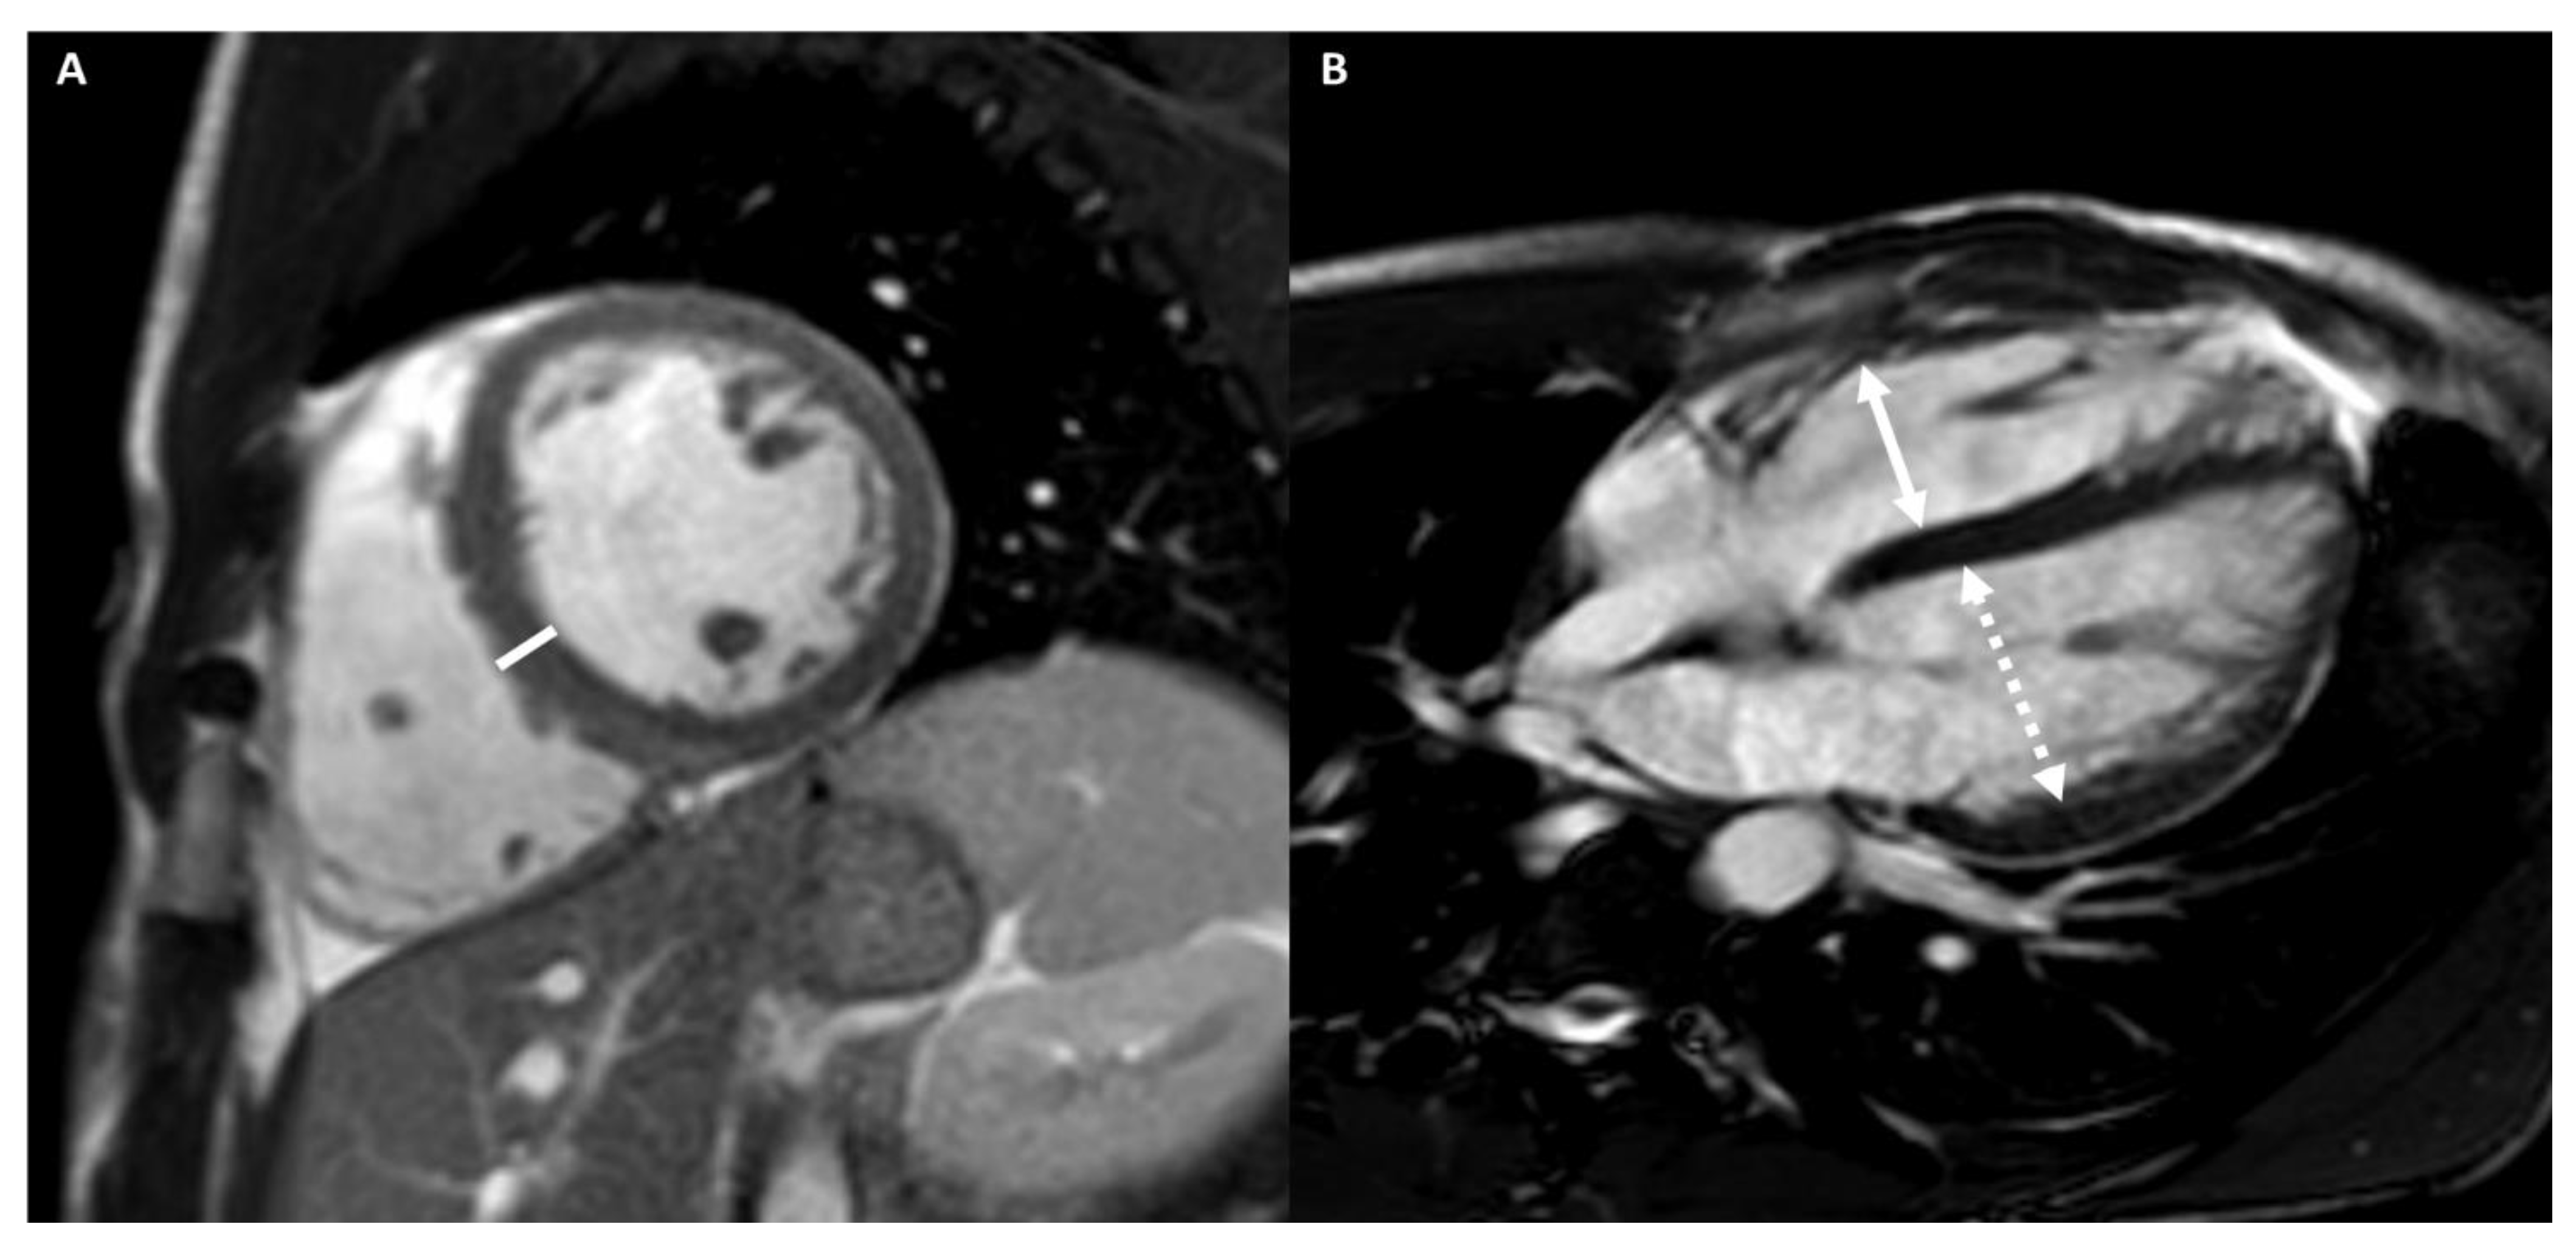

4.2.3. Cardiac Imaging: AH vs. Left Ventricular Non-Compaction

| Trabeculation | Increased | Increased | Increased | NC/C > 2.3 in two cardiac segments | - | - | - |